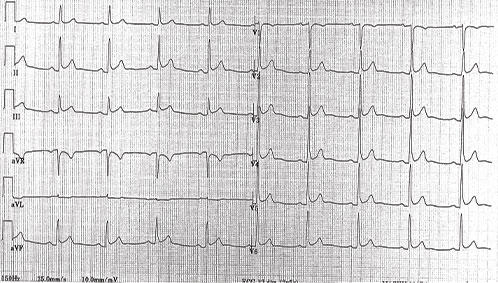

1 ECG

Il est à répéter car il peut être normal. Il montre :

• des anomalies diffuses non systématisées sans image en miroir évoluant en 4 stades (cf. fig. 20.1) :

– stade I : sus-décalage ST concave vers le haut, ondes T positives le 1er jour,

– stade II : ondes T plates entre la 24e et la 48e heure,

– stade III : ondes T négatives la 1re semaine,

– stade IV : normalisation au cours du 1er mois ;

• d’autres signes :

– sous-décalage de PQ présent à la phase initiale ;

– tachycardie sinusale, extrasystole atriale, fibrillation atriale, flutter atrial ;

– microvoltage en cas d’épanchement abondant (amplitude QRS < 5 mm et < 10 mm respectivement dans les dérivations périphériques et précordiales).

Fig. 20.1. ![]() Électrocardiogramme d’une péricardite aiguë avec sous-décalage de PQ et sus-décalage du segment ST concave vers le haut et diffus.

Électrocardiogramme d’une péricardite aiguë avec sous-décalage de PQ et sus-décalage du segment ST concave vers le haut et diffus.